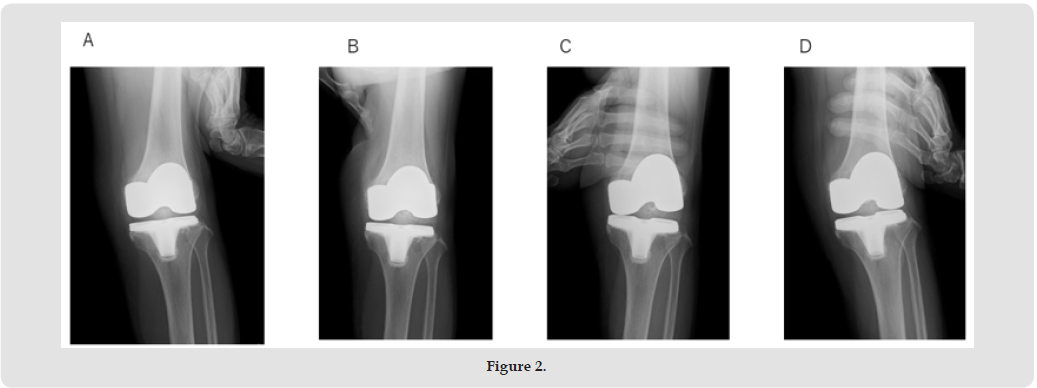

A 77-year-old woman with osteoarthritis in her left knee underwent Zimmer Persona posterior stabilizer type TKA in another hospital about 3.5 years ago. Three years later, she experienced severe pain and a locking sensation in her left knee while shopping. A swelling and tenderness were observed in the left knee. A joint puncture was then performed. The aspirated fluid resembled blood. The bacterial culture was negative. Subsequently, severe pain and a locking sensation in the knee appeared occasionally. Therefore, she was referred to our department for surgery. Her history was unremarkable. A physical examination revealed swelling and slight local heat of the left knee. Anterior instability was not observed, but varus and valgus instability were eminent. The range of motion (ROM) was 0 to 123o. The knee-rating scale of the Hospital for Special Surgery (HSS) was 53. Radiographs showed that the tibiofemoral joint was not dislocated, and loosening of the implants was not found (Figures 1A & 1B). In the stress radiographs, varus and valgus instabilities (ext. 0o, flex. 30o) were noted (Figures 2A-2D).